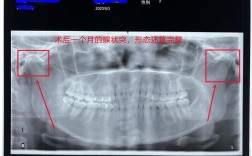

- 全口曲面断层片:了解全口牙列情况。

- 术后定期(如1个月、3个月、6个月、1年、2年)进行临床检查和影像学评估(根尖片、CBCT)。

- 影像学: 观察牙根吸收情况(最常见并发症)、骨愈合情况、根尖周骨质密度、根管钙化情况。